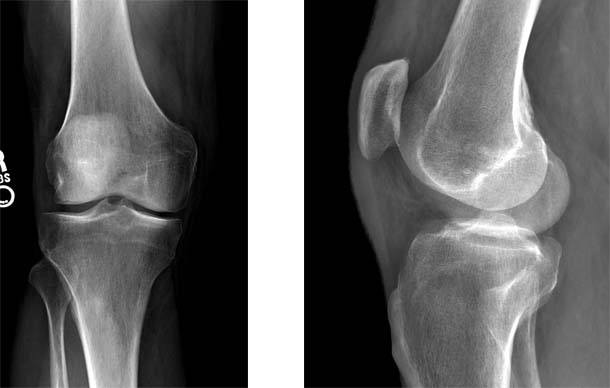

1.The standard radiographs of his knee show minimal evidence of arthritis.